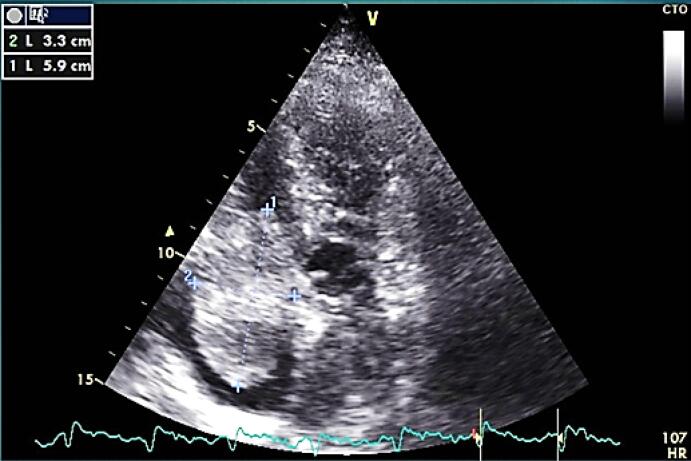

我们知道,心脏黏液瘤是最主要的心脏肿块之一,但这种类型的肿瘤的实验室结果是非特异性的,诊断是通过影像学。在这个病例中,我们报告了一名61岁的男子,他最近出现呼吸困难的病史,实验室检查显示红细胞增多症伴血小板减少症。腹部超声、骨髓穿刺及活检未见明显诊断,但超声心动图发现右心房有大肿块。在心脏病专家和心脏外科医生会诊后,计划进行手术切除,之后血小板减少症得到解决。在这个病例报告中,我们想写心脏黏液瘤和血小板减少症之间罕见的相关性,并表明早期诊断和治疗这种疾病可以帮助和完全治愈患者的抱怨。

As we know, cardiac myxoma is one of the most primary cardiac masses but laboratory findings in this type of tumor is non-specific and the diagnosis is by imaging. In this case we have reported a 61 year old man came to the emergency ward of hospital with history of recent onset dyspnea and The Laboratory finding indicates polycythemia with thrombocytopenia. Ultrasonography of abdomen and bone marrow aspiration and biopsy revealed no significant diagnosis but on echocardiography a large sized mass was detected in right atrium. After cardiologist and cardiac surgeon consultation the plan was to surgical Excision and after that the thrombocytopenia has been resolved. In this case report we want to write about a rare correlation between cardiac myxoma and thrombocytopenia and show that early diagnosis and treatment of the disease can help and totally cure complaints of patient.